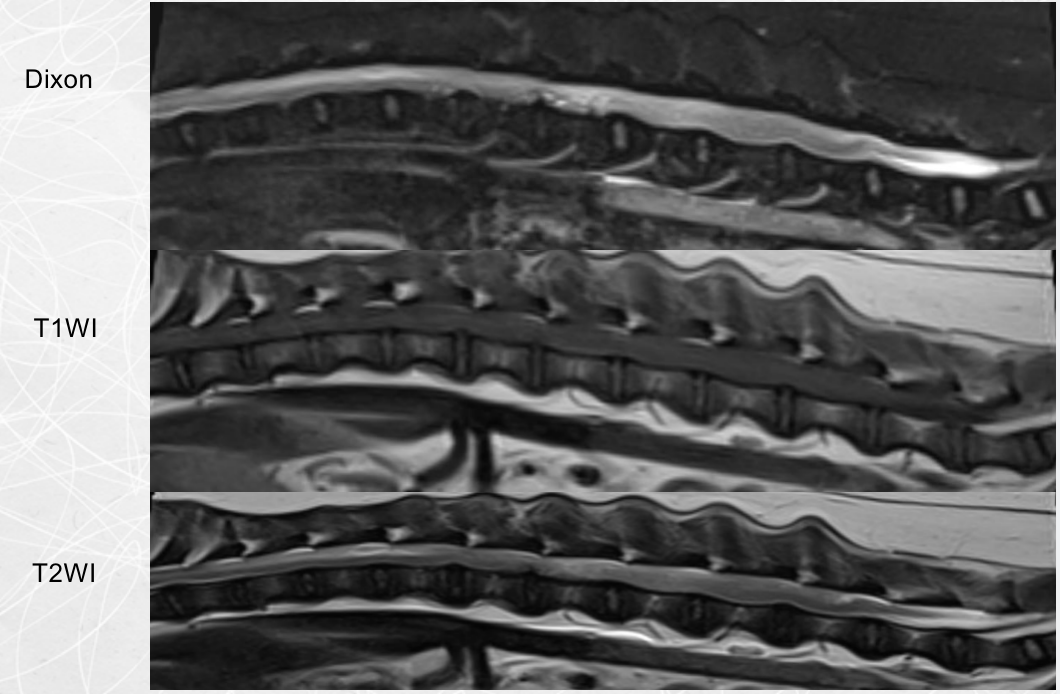

MRI检查

胸腰椎核磁检查

检查部位:胸椎/腰椎MRI平扫检查

检查序列:T1序列,T2序列,压脂序列,压水序列,共218张图⽚⽤于结果判读。

影像所⻅:

1、L1-L2蛛网膜下腔脑脊液连续性消失,椎管内脊髓左腹侧可见T1WI等信号、T2WI低 信号占位,其尾侧(L2中段水平)可见T2WI高信号结构,脊髓受压迫向右背侧移位,L2段 脊髓T2WI信号增强。

2、 T13-L1脊髓腹侧可见T1WI等信号、T2WI低信号结构。3、T13-L2、L4-L5椎间盘呈T2WI低信号。

影像印象:

1、汉森II型椎间盘突出(L1-L2),压迫脊髓及左侧神经根,后段脊髓损伤/水肿,出 血可疑,结合临床评估。

2、轻度汉森I型椎间盘突出(T13-L1)。

3、胸腰椎多处椎间盘变性。

MRI(磁共振)

MRI(磁共振)属无创伤、无射线检查 ,也无生物学损害,且软组织对比分辨率最高, 它可以清楚地分辨肌肉、肌腱、筋膜、脂肪等软组织

SIEMENS MAGNETOM ESSENZA Galaxy

临床型1.5T磁共振